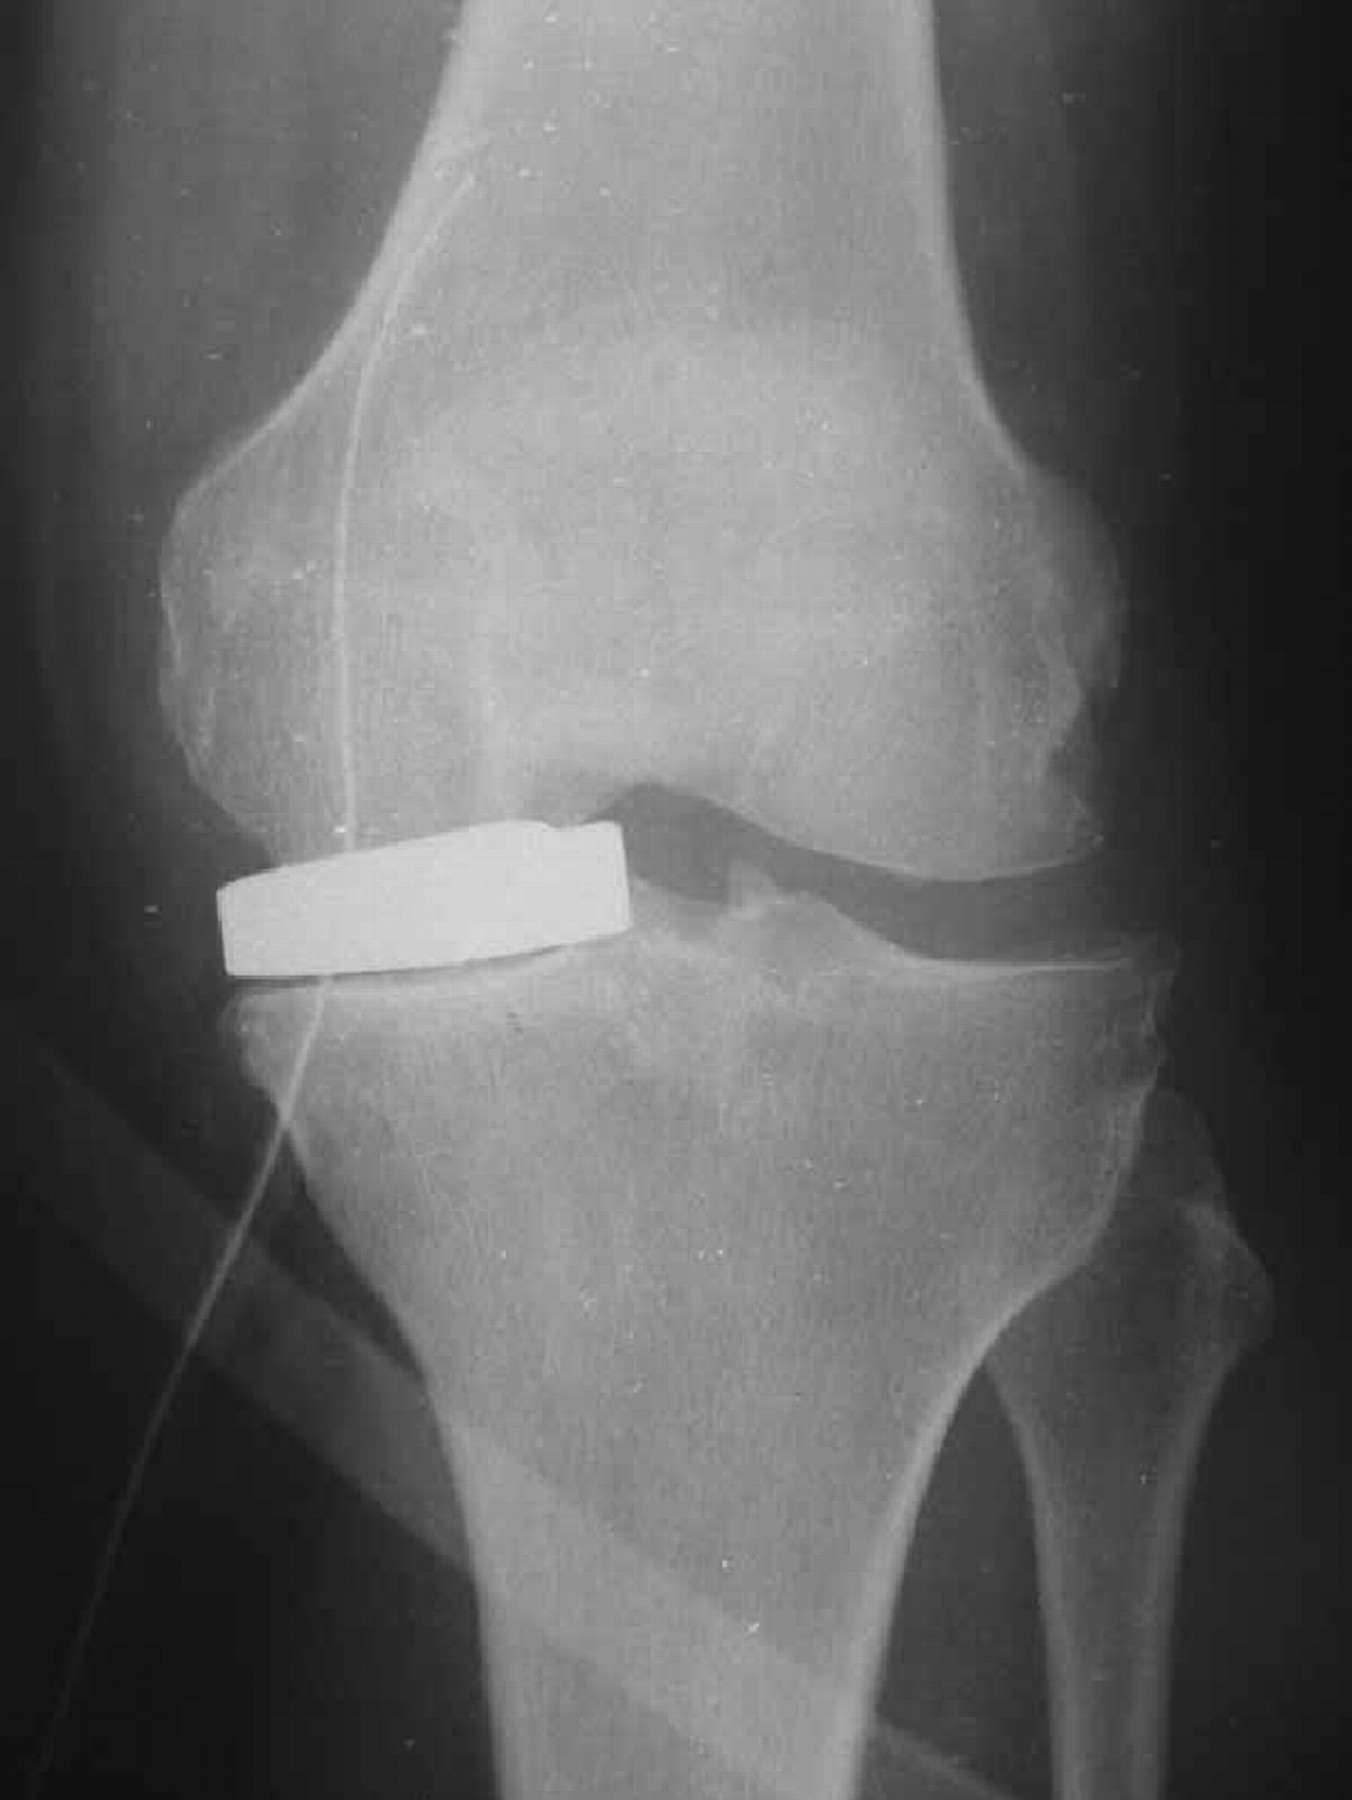

The Unispacer knee implant Bone & Joint Plastic Spacer In Knee Replacement In most cases, your surgeon will also remove part of the underside of the kneecap. The first operation is to remove the old prosthesis and insert a block of cement with. A plastic spacer is placed between the. In a total knee replacement, the arthritic portion of the joint is replaced with metal components. This spacer is treated with antibiotics. Plastic Spacer In Knee Replacement.

Cureus TwoStage Total Knee Arthroplasty Revision With Extended Antibiotic Spacer Use Plastic Spacer In Knee Replacement This spacer is treated with antibiotics to fight the infection. It features a metal femoral component that rides on a polyethylene. I have had several knee surgeries to replace my spacer due to the fact my ligaments and tendons wouldn't keep my knee stable. The causes of revision total knee replacement are varied. This is the most common type of. Plastic Spacer In Knee Replacement.

Infected Total Knee Replacement Cement Spacer Musculoskeletal Key Plastic Spacer In Knee Replacement A plastic spacer is placed between the. A plastic spacer is inserted into the space between the metal implants, for ease of movement. The causes of revision total knee replacement are varied. There is a subset of these revision cases (poly wear and some cases of instability for. I have had several knee surgeries to replace my spacer due to. Plastic Spacer In Knee Replacement.

Antibiotic Spacers for the Treatment of Infected Total Knee Arthroplasty Cases Musculoskeletal Key Plastic Spacer In Knee Replacement This is the most common type of implant. A plastic spacer is placed between the. The first operation is to remove the old prosthesis and insert a block of cement with. The causes of revision total knee replacement are varied. It features a metal femoral component that rides on a polyethylene. This spacer is treated with antibiotics to fight the. Plastic Spacer In Knee Replacement.